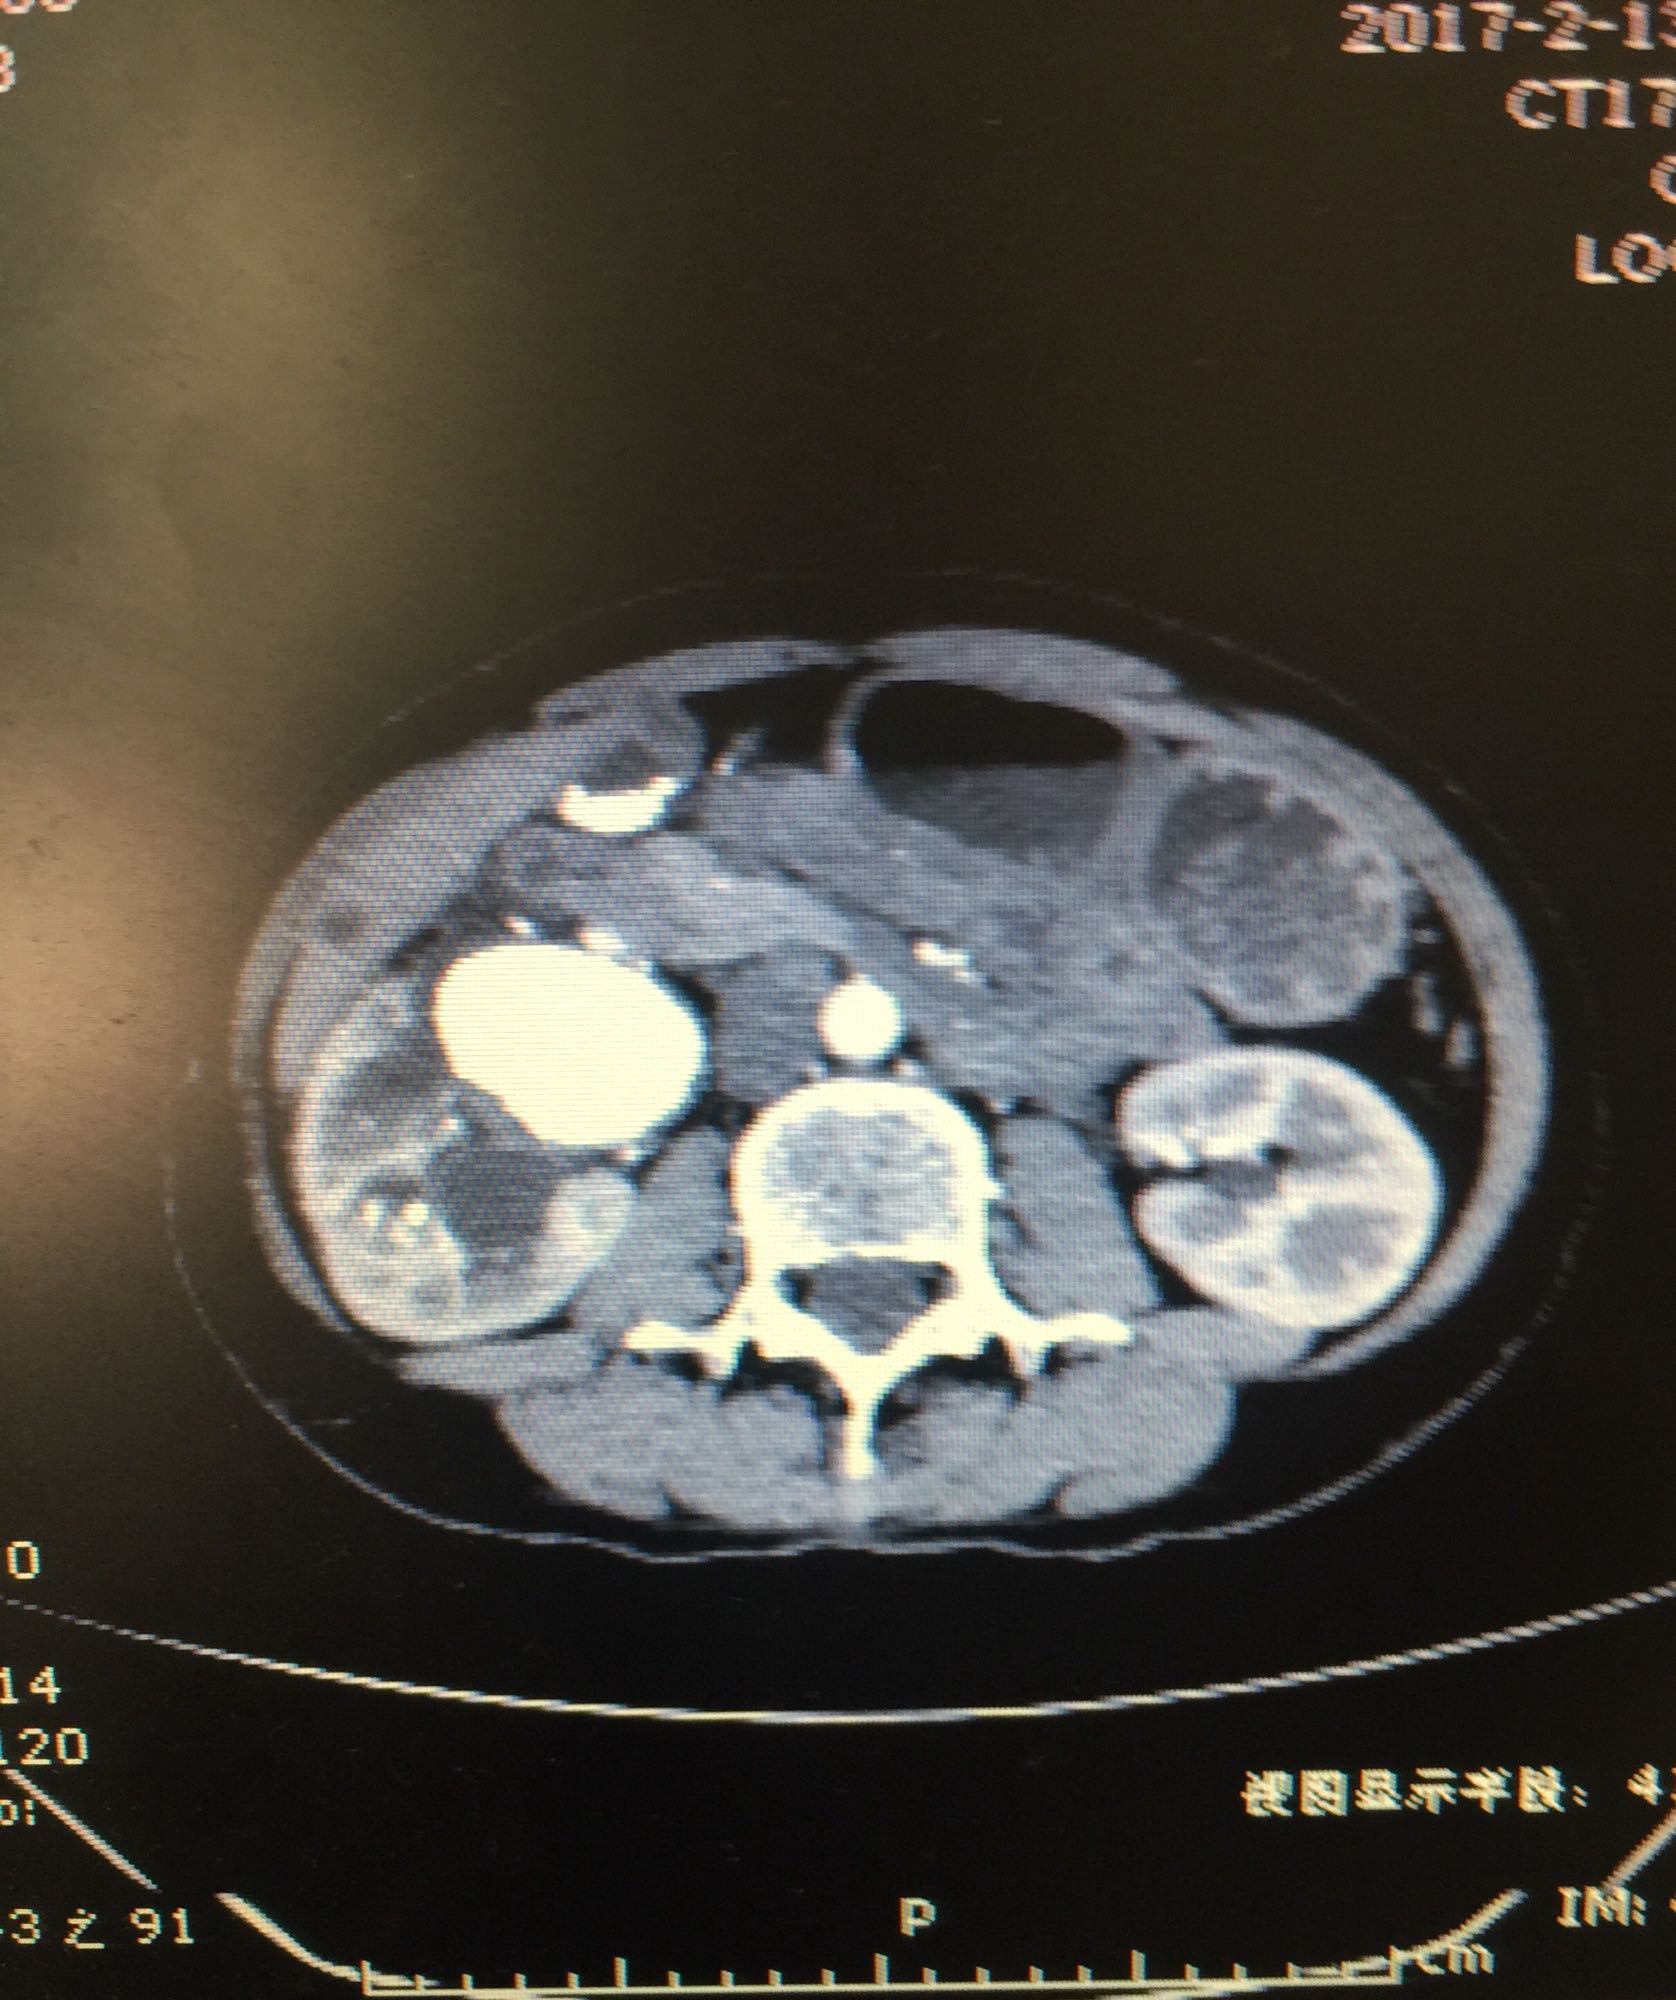

右侧肾脏巨大铸型结石一例

肾盂积水伴输尿管肾盂连接处梗阻 肾结石

60余岁老年男性 因右侧腰痛伴发热1周入院 1周前开始出现右侧腰部胀痛,伴低热,无尿频尿急及肉眼血尿,无其他不适症状 既往高血压,无糖尿病及其他病史

查体右侧肾区轻度叩痛,余症状阴性 辅助检查尿白细胞+++,肾功正常,甲状旁腺激素正常,钙磷比例正常范围

右侧肾脏巨大铸型结石,右肾盂输尿管连接部狭窄? 拟完善GFR测定后决定下一步治疗方案,目前倾向于开放手术。

该患者结石大,且负荷大部分位于肾盂,肾盂几乎被填满,所以考虑是否有右侧输尿管肾盂连接部狭窄可能,结石负荷大,结合上述情况可行开放手术,一期整形 。 但若为UPJO,患者肾脏积水轻,肾脏皮质厚,肾功影响小,可能性相对小。行PCN结合超声吸附,一期清理肾盂内结石应该问题不大。 对于该患者的治疗,不知大家意见如何?